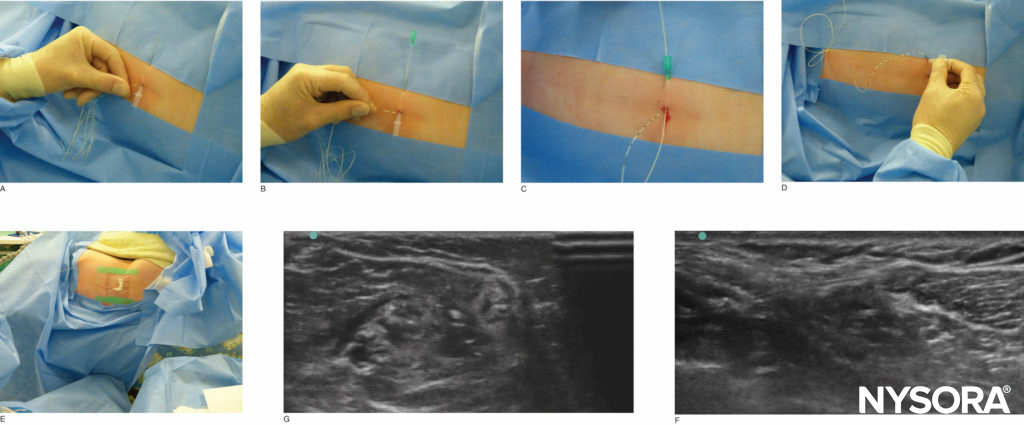

Infective complications are rare and also less common than in adults; nevertheless, a strict aseptic technique should be used when placing peripheral nerve catheters. It is debatable whether it is helpful to make a space around the nerve for the catheter to be inserted into. With US, an advantage of making a space with local anesthetic is that the anesthesiologist knows that he or she has at least provided a reliable single injection of local anesthetic. The position of the catheter is confirmed by using a neurostimulating catheter or US. However, neurostimulating catheters are expensive, and their advantages are insignificant. When using US, it is often helpful to identify the catheter tip by scanning in both the transverse and longitudinal planes; local anesthetic or saline can then be injected and the spread assessed. Generally, no more than 2–3 cm of the catheter is inserted beyond the needle tip.

To ensure catheter security, tunneling should be performed for the majority of techniques (Figure 2). In addition, tissue glue should be applied to the original and secondary puncture sites to stop local anesthetic solution from leaking during infusion. Leakage of infusion causes the dressing to become wet and lift off the skin, leading to catheter dislodgement. Indermil or Dermabond glue can be used; the advantage of the latter is that it can be easily removed with yellow paraffin. It is usually a good idea to flush the catheter once it is tunneled and secured to ensure no kink has formed under the skin. The local anesthetic pump should be run intraoperatively so that any occlusion is detected prior to the patient being recovered.

FIGURE 2. Tunneling of the popliteal catheter. The image in (F) illustrates an in-plane approach, whereas (G) illustrates an out-of-plane approach.